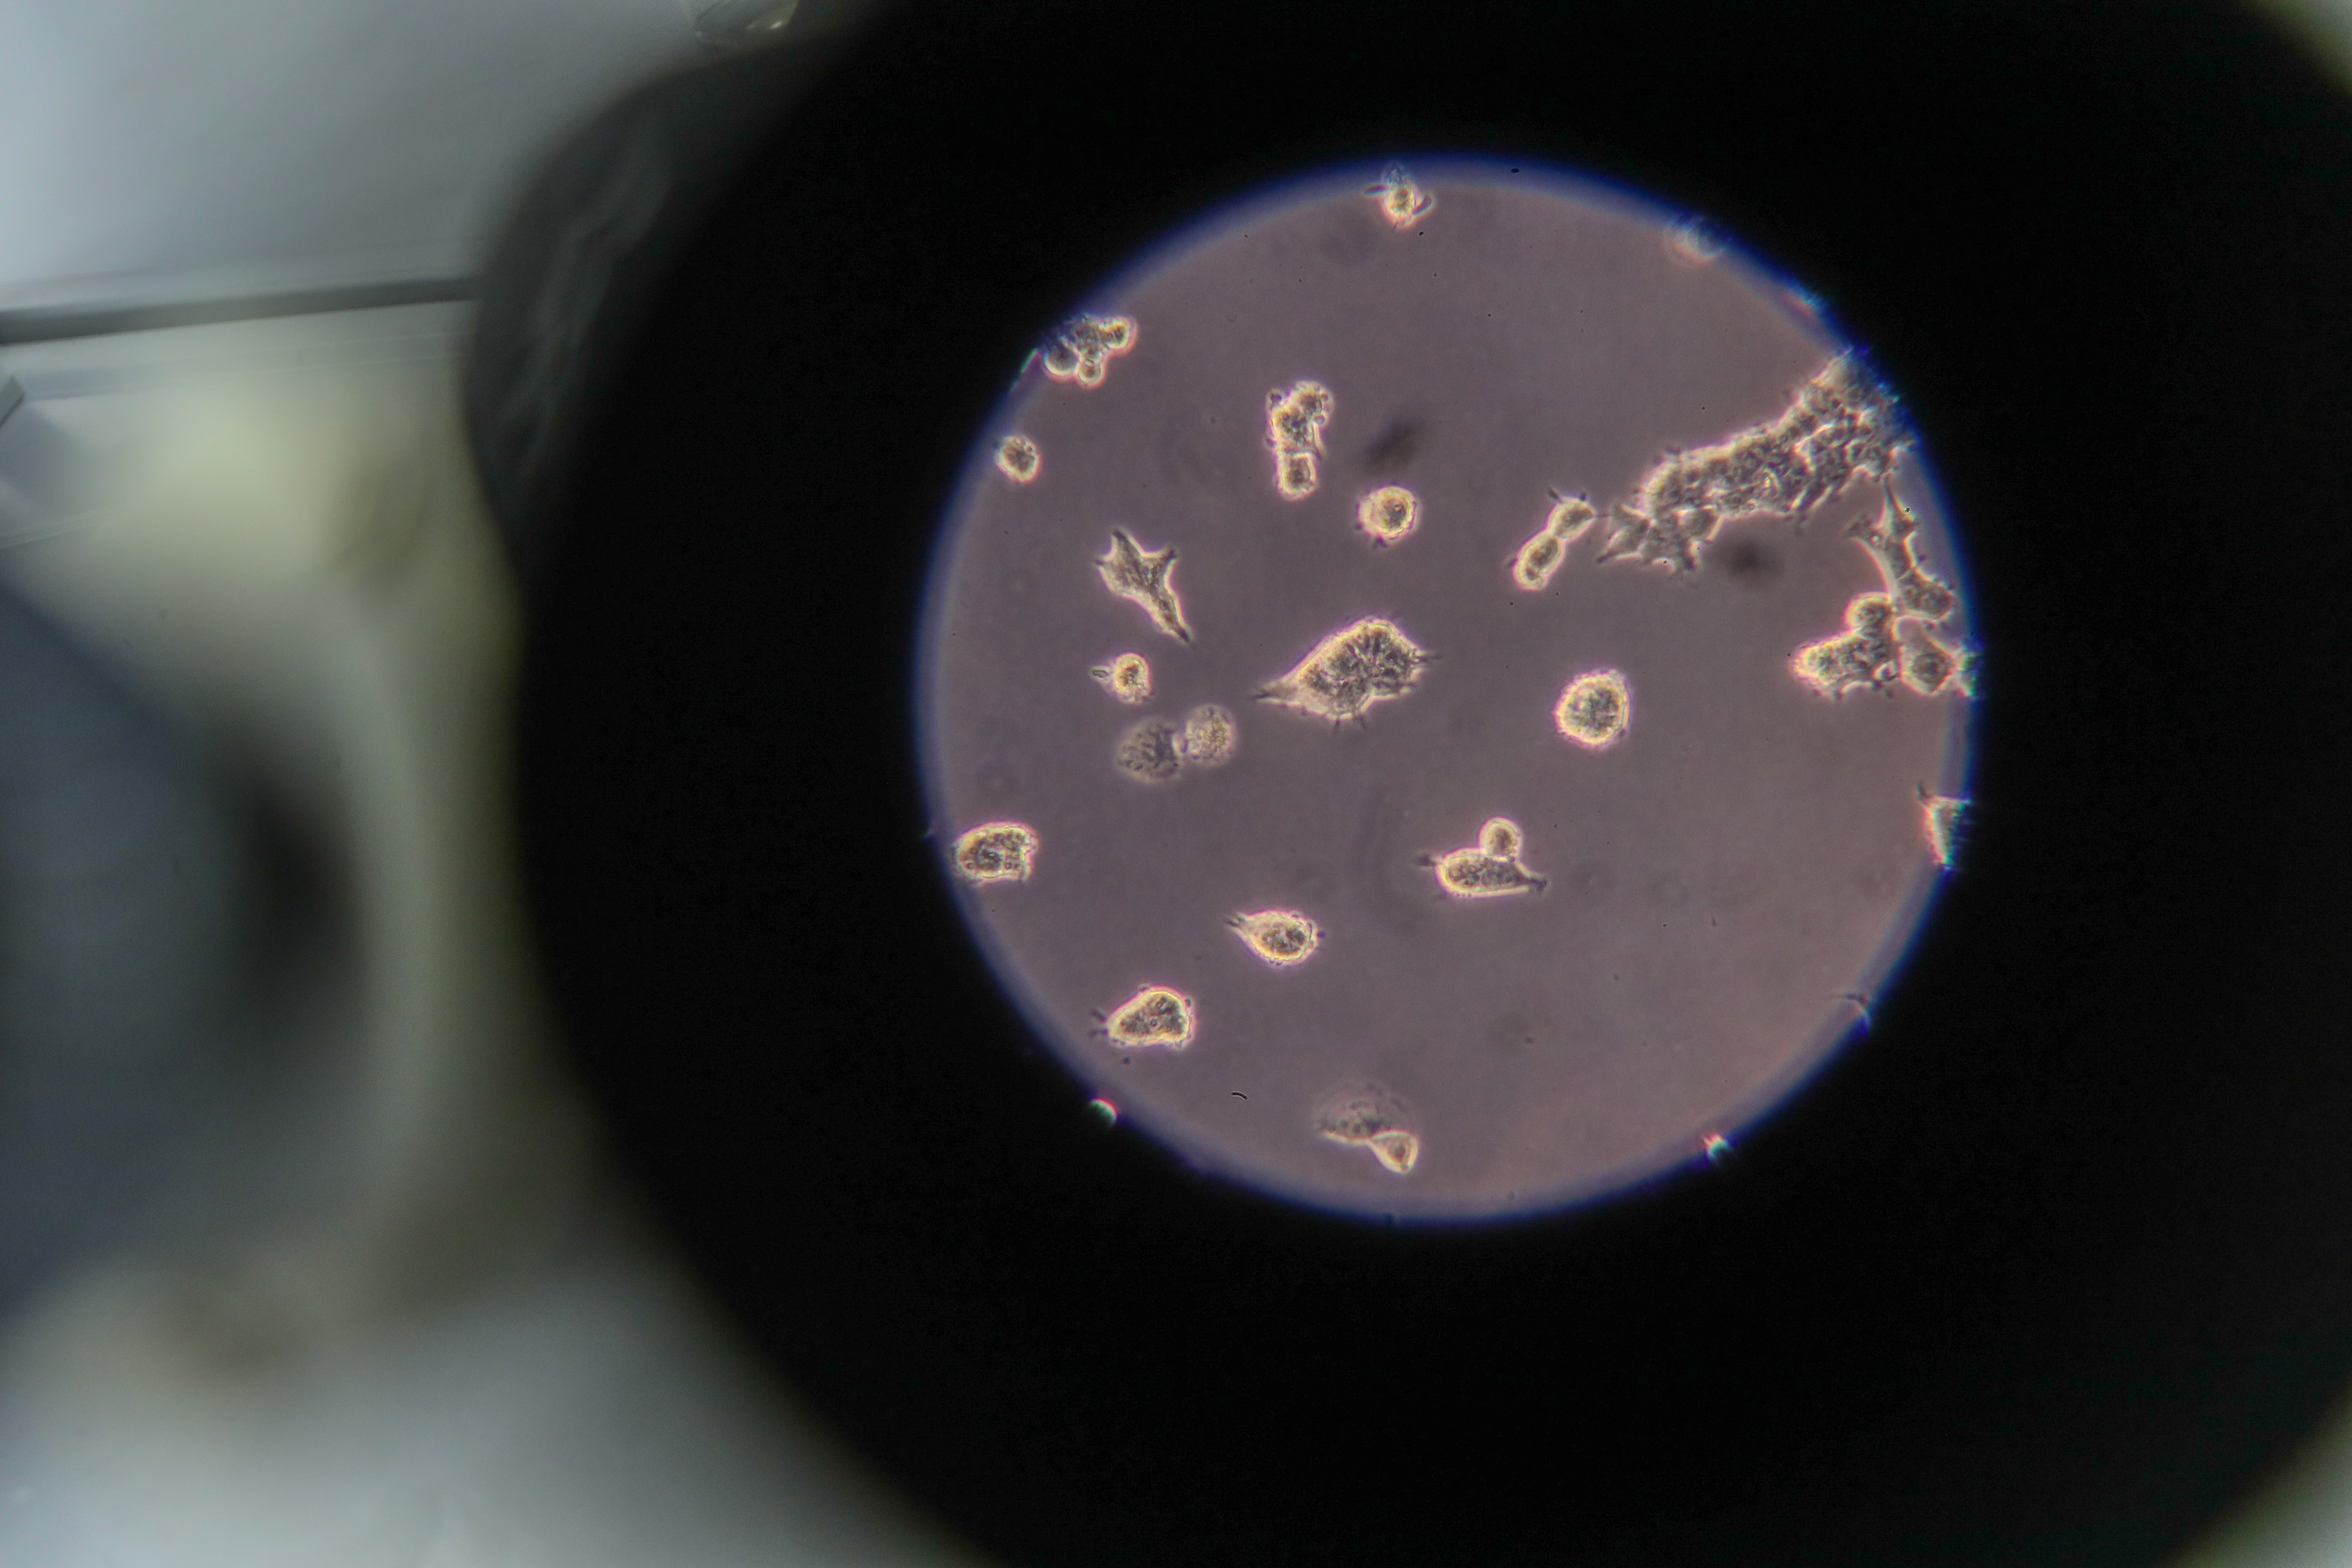

MOSCOW, January 22. /TASS/. American and British biologists have discovered that embryo cells at the early stages of development will be highly susceptible to the coronavirus attacks if its particles manage to enter the system of a pregnant woman. The results of their observations were published in an article in the bioRxiv electronic library. "Our finding that pre-implantation embryos are permissive to SARSCoV-2 entry highlights a potential vulnerability of these embryos in vivo. Additionally, the data presented here should prompt careful review of procedures surrounding in vitro fertilization during the COVID-19 pandemic and its aftermath," the researchers wrote. Last February, Chinese biologists detected signs that the SARS-COV-2 coronavirus that caused the pandemic of COVID-19, may infect placental cells of pregnant women. This made scientists suspect that the pathogen may spread intrauterinally, entering an embryo through a placenta. On the other hand, subsequent observations demonstrated that such cases are rare. Additionally, the scientists couldn’t register visible consequences of the coronavirus infection penetrating tissues of an embryo. Such an uncertainty resulted in many arguments whether the SARS-CoV-2 virus is dangerous for unborn children. Consequences of infection A group of American and British molecular biologists led by researcher Mauricio Montano of the Gladstone Institutes in San Francisco, USA for the first time ever tried to obtain direct answers to this question by experimenting with surplus embryos from fertility treatment and in vitro fertilization, donated strictly for research, and analogues of the SARS-CoV-2 particles. The biologists were interested in two things - whether the ACE2 receptors and the TMPRSS2 proteases, critically important for the spread of the coronavirus, are present on the surface of embryonal cells, and if so, whether fragments of the SARS-CoV-2 membrane can penetrate them. As it turned out, the answer was in the affirmative for all embryos obtained from donors with very different ethnic backgrounds. Their cells indeed were developing a large amount of ACE2 and TMPRSS proteins, and models of the coronavirus particles were easily penetrating them, resulting in their mass death despite the models’ inability to reproduce. Such experimental results, as the researchers noted, indicate that the embryos will be particularly susceptible to the coronavirus infection at the early stages of their development when they are not protected anymore by a special glycoprotein membrane which surrounds unfertilized ova while the placenta and the own immune system haven’t been formed yet. For this reason the scientists propose to think about additional measures of precaution in the operations of fertility clinics as well as to study in detail the effect of the SARS-CoV-2 virus on embryos of various animal models. Read more